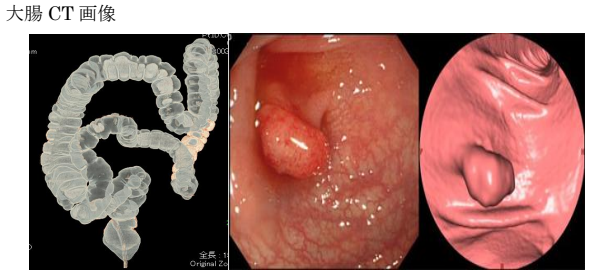

大腸CT検査について

- 内視鏡を使わない新しい検査です

- マルチスライスCT装置により3次元画像を作成して正確な検査が行えます

- 内視鏡挿入や造影剤注入の必要がないため苦痛の少ない検査です(吸収・排出されやすい炭酸ガスの注入は必要となります)

- 検査部屋入室から退室 まで20分程度の検査です

内視鏡検査

当院のマルチスライスCT装置では、鮮明で高精度な画像を撮影でき、さらに3D画像によって大腸内部を立体的に観察することが可能です。

これにより、見落としの少ないより正確な評価につながります。